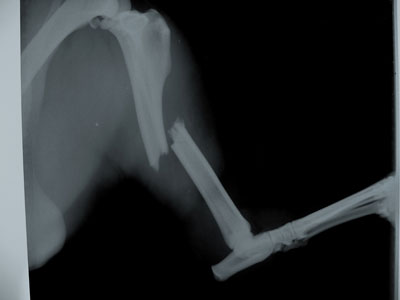

Μεγαλόσωμος σκύλος 30kg 1 έτους με τέλειο κάταγμα μεσότητας διάφυσης δεξιάς κνήμης.Το χειρουργείο πραγματοποιήθηκε στις 06/10/09.

Μεταλλική πλάκα 3,5mm τοποθετήθηκε στην έσω επιφάνεια της κνήμης με 8 κοχλίες 3,5mm.